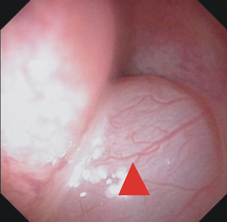

鄭先生是35歲男性,本身無特殊慢性疾病,近年來因為長年聞不到味道,合併有鼻塞情況來本院門診求診,經鼻咽內視鏡診察後發現雙側鼻腔內有鼻息肉(如:圖一),同時合併有膿鼻涕及鼻涕倒流情況(如:圖二)。電腦斷層檢查亦發現兩側鼻竇均有嚴重鼻息肉以及蓄膿情況 (如:圖三),由於過去數月在診所接受藥物治療效果不彰,因此經醫師建議接受電磁導航鼻竇內視鏡手術治療。

圖一、鼻咽內視鏡發現右側中鼻道鼻息肉(紅色三角形處)